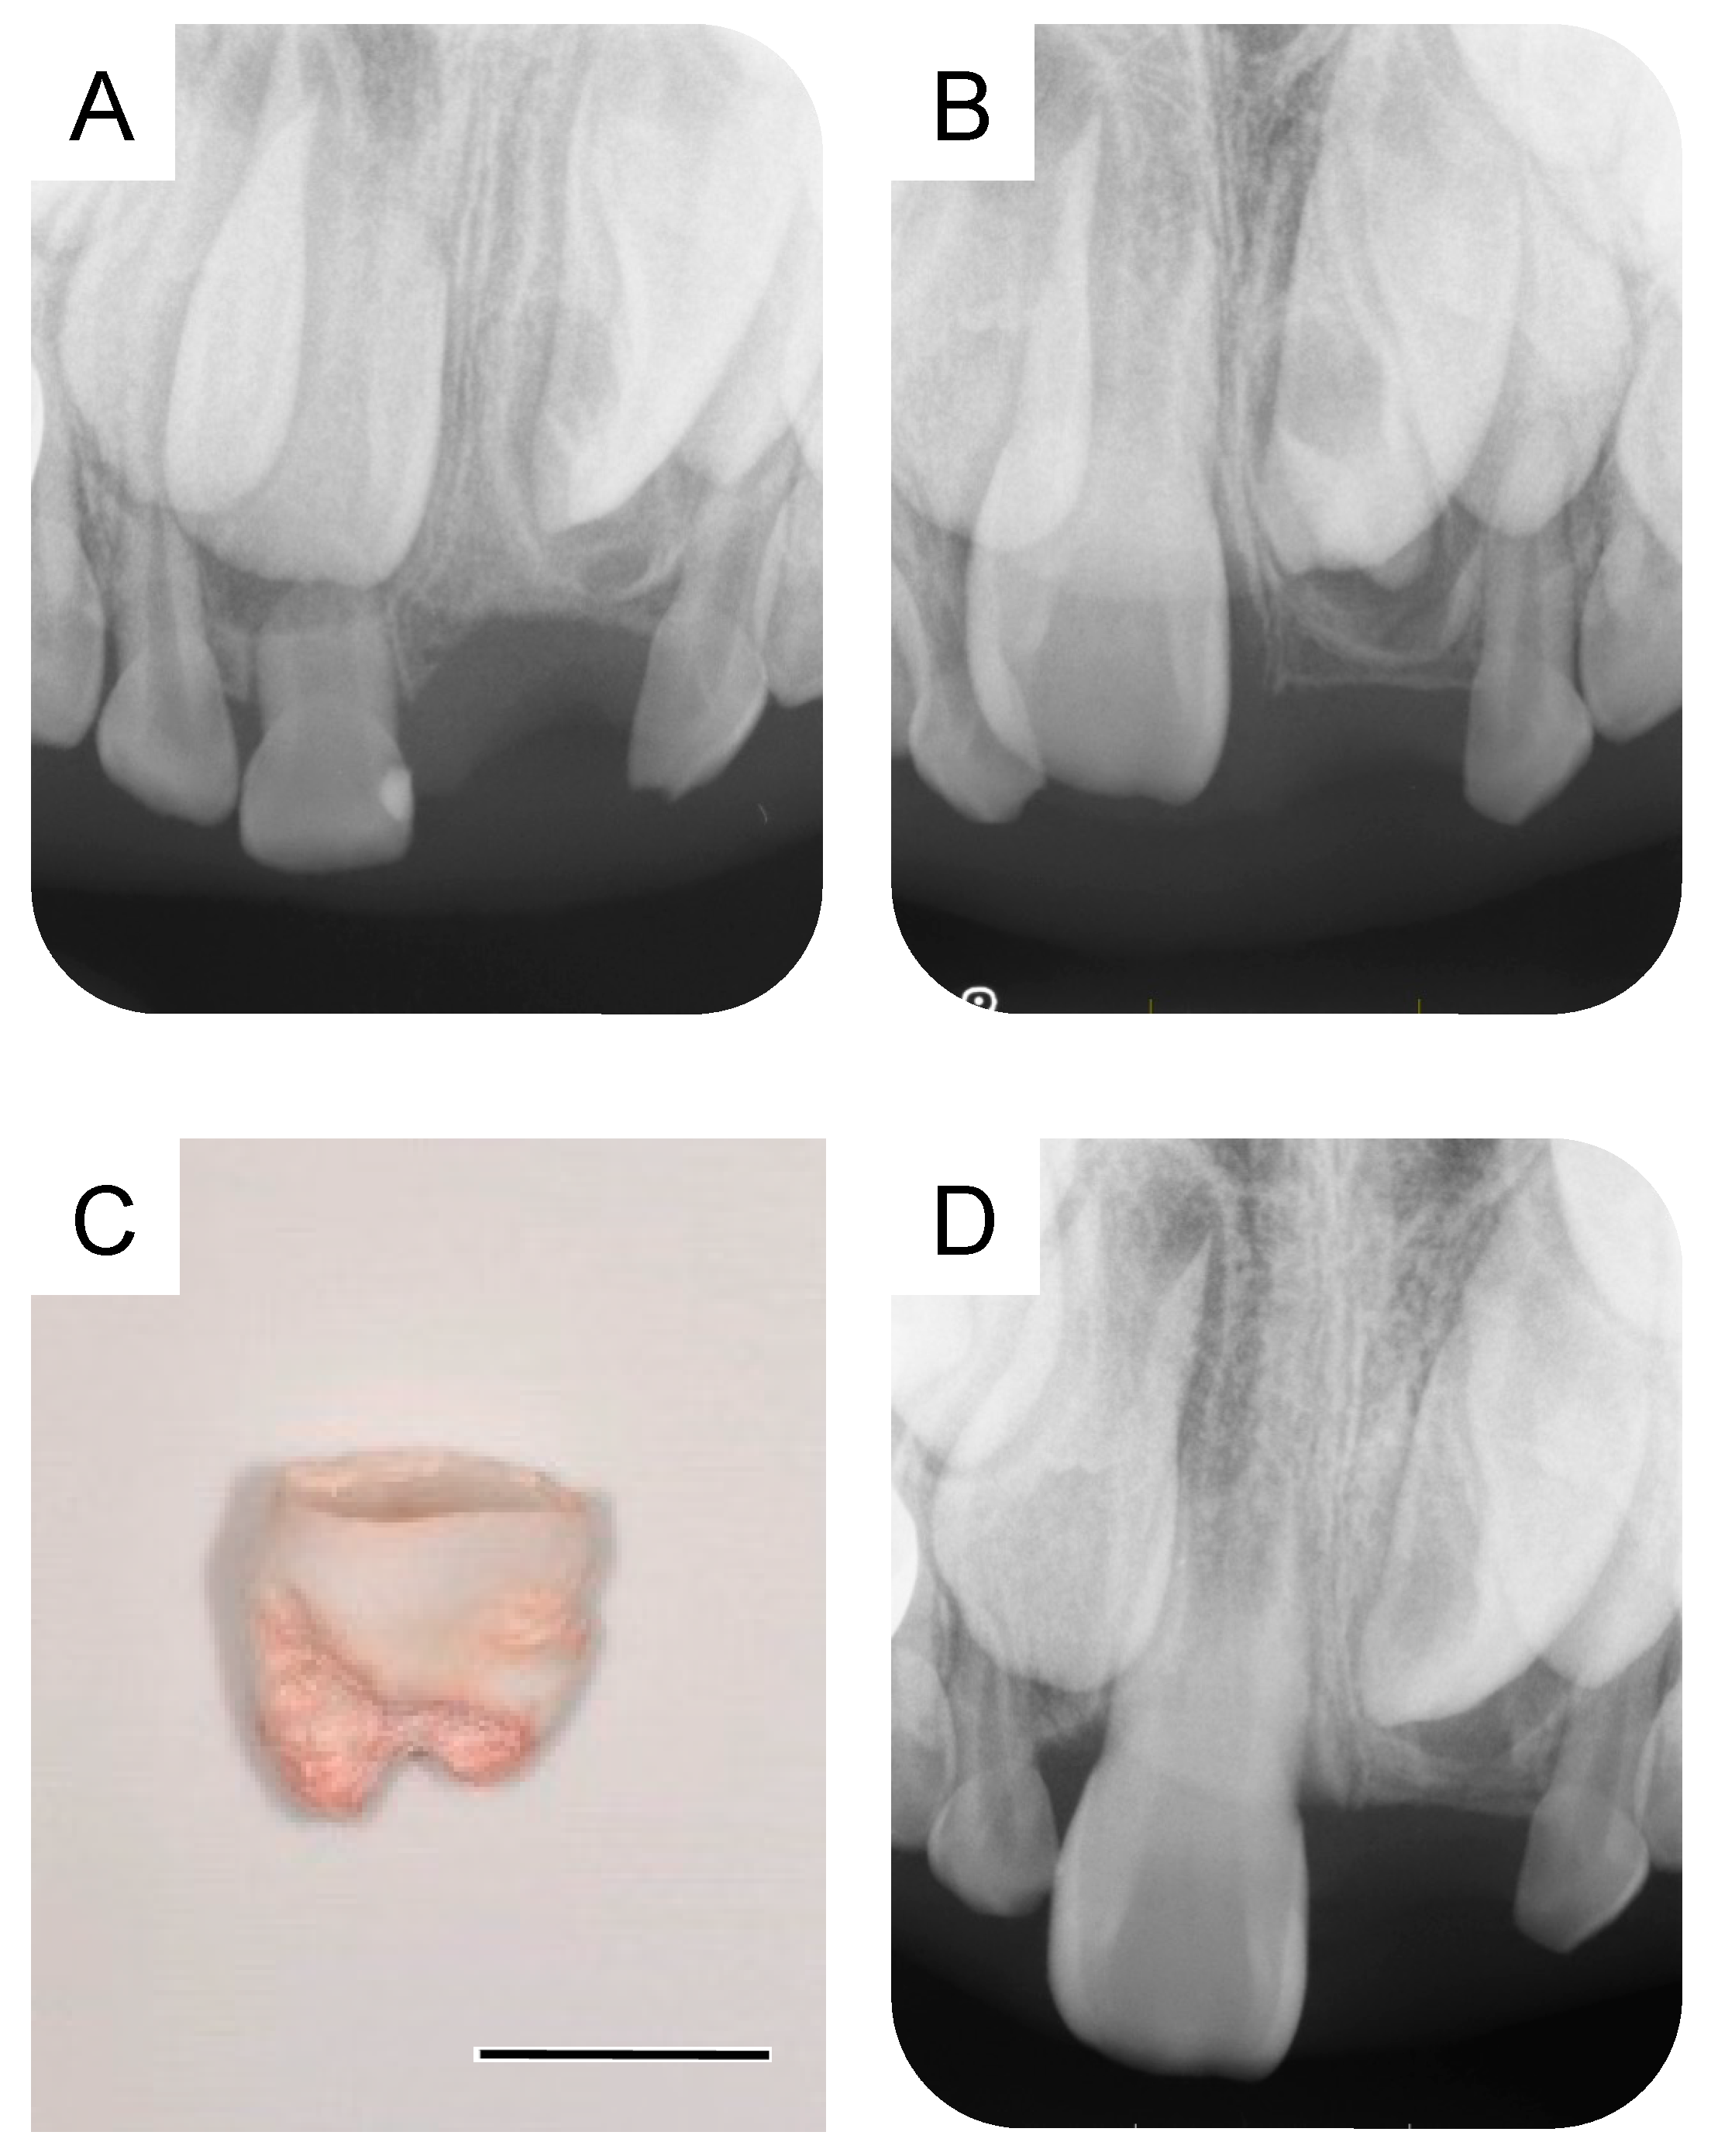

By the time the patient was aged 8 years and 2 months, the permanent maxillary left central incisor had not erupted in the oral cavity (Figure 3A). A periapical radiograph revealed the presence of a calcified tissue near the crown of the permanent maxillary left central incisor (Figure 3B). Considering the difference in the eruption time of the bilateral permanent maxillary central incisors, we decided to take an immediate surgical approach. One month later, we surgically removed the calcified tissue and the bone covering the permanent maxillary left central incisor under physical restraint. The extracted calcified tissue measured 5 mm × 5 mm (Figure 3C). Histopathological examination showed the presence of a tooth-like structure with enamel, dentin, pulp, and reduced enamel epithelium, confirming the diagnosis of a third supernumerary tooth (Figure 4).

Figure 3. Extraction of the third supernumerary tooth. (A) Intraoral photograph at the age of 8 years and 2 months. (B) Periapical radiograph showing the third supernumerary tooth at the age of 8 years and 2 months. (C) Extracted calcified tissue, which was later diagnosed as the third supernumerary tooth. Scale bar: 5 mm.